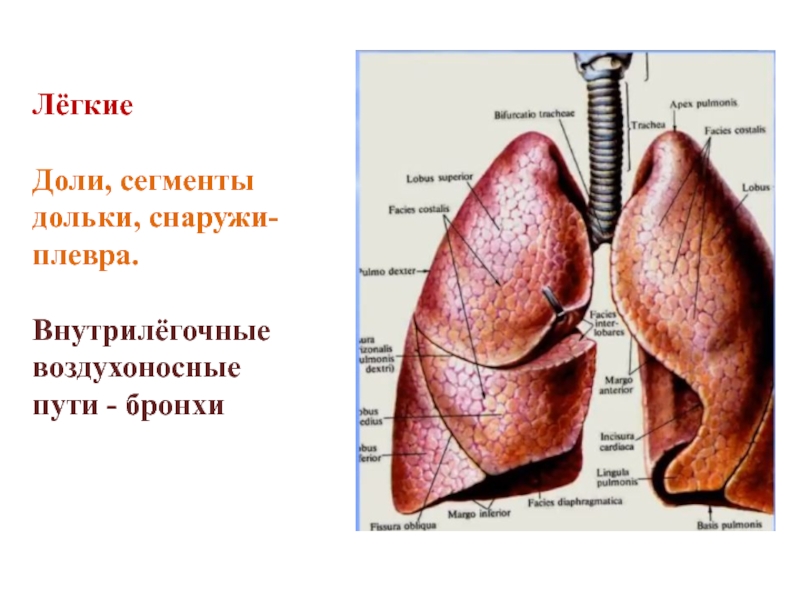

Анатомические изображения сегментов легких различных животных

Раздел: Другие животные